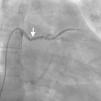

Case reportA 44-year-old man presented with several weeks of palpitations. He also described symptoms of dyspnea with mild exertion and substernal chest discomfort at rest. He had a history of long-standing systemic hypertension. The 12-lead ECG showed atrial fibrillation with rapid ventricular rate. His 2D Doppler echocardiogram revealed a mildly enlarged RA and right ventricle (RV). He subsequently underwent right and left heart catheterization with selective coronary angiography. Right and left heart catheterization with a full oximetry run to calculate shunts revealed Qp/Qs of 1.3. Selective coronary angiography was performed using right radial artery access, and showed no significant coronary disease. However, angiography of the aortic arch showed a single trunk takeoff for the large vessels from the aortic arch (Figure 1). Using right femoral vein access, a 5-Fr multipurpose diagnostic catheter was advanced into the upper (Figure 2) and middle (Figure 3) right pulmonary veins as they opened into the superior vena cava (SVC). To exclude any possible associated atrial septal defect, an MP-1 catheter was engaged into what proved to be a coronary-cameral fistula (CCF) opening into the RA separately from the coronary sinus (Figure 4), the CCF went from the coronary vein to the RA and the coronary sinus was also filled with contrast retrogradely from the vein (Figure 4). Pulmonary angiography using a 5-Fr pigtail catheter showed a moderately dilated pulmonary trunk (Figure 5). Following consultations with the cardiothoracic surgery and pediatric cardiology teams, it was felt that the best course of management would be to follow the patient clinically with serial echocardiography, as there was no significant right-to-left shunt.

SS is a complex form of PAPVR, which is a connection failure between the right pulmonary veins and the LA during fetal development. Variations in PAPVR include the right pulmonary veins draining into the SVC-LA junction, RA, or IVC, or as in our case, separately to a high SVC. In SS, an anomalous right pulmonary vein generally draining the entire right lung but occasionally the middle and superior lobes, may descend in a cephalad-to-caudal direction toward the diaphragm with a crescent (scimitar) shape. This vein then curves sharply to the left just above or below the IVC-RA junction.8 The anomalous right pulmonary venous trunk usually courses anterior to the hilum of the right lung and connects to the IVC just superior to the orifices of the hepatic veins. Rarely, it drains into the left atrium, with normal venous return.9

In this patient, the right upper and middle pulmonary veins drained into the high SVC and then ultimately into the RA, leading to increased pulmonary circulation as shown by the enlarged right chambers and main pulmonary artery.